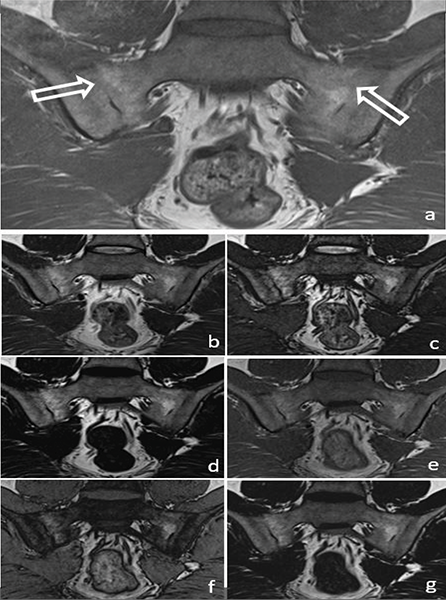

In the evaluation of chronic sacroiliitis, there was no significant difference in the detection of PFD (P = 0.08) (Figure 2) or ankylosis (P = 0.42) (Figure 3) among standard T1W, T1W–T2W Dixon (FO, IP and OP) images.

Figure 3

A 34‑year‑old male patient with ankylosis (arrow) in both sacroiliac joints on a T1W image (a) (arrows). Ankylosis can be easily seen in the T2W Dixon IP (b), T2W Dixon OP (c), T2W Dixon FO (d), T1W Dixon IP (e), T1W Dixon OP (f) and T1W Dixon FO (g) images shown in the figure.